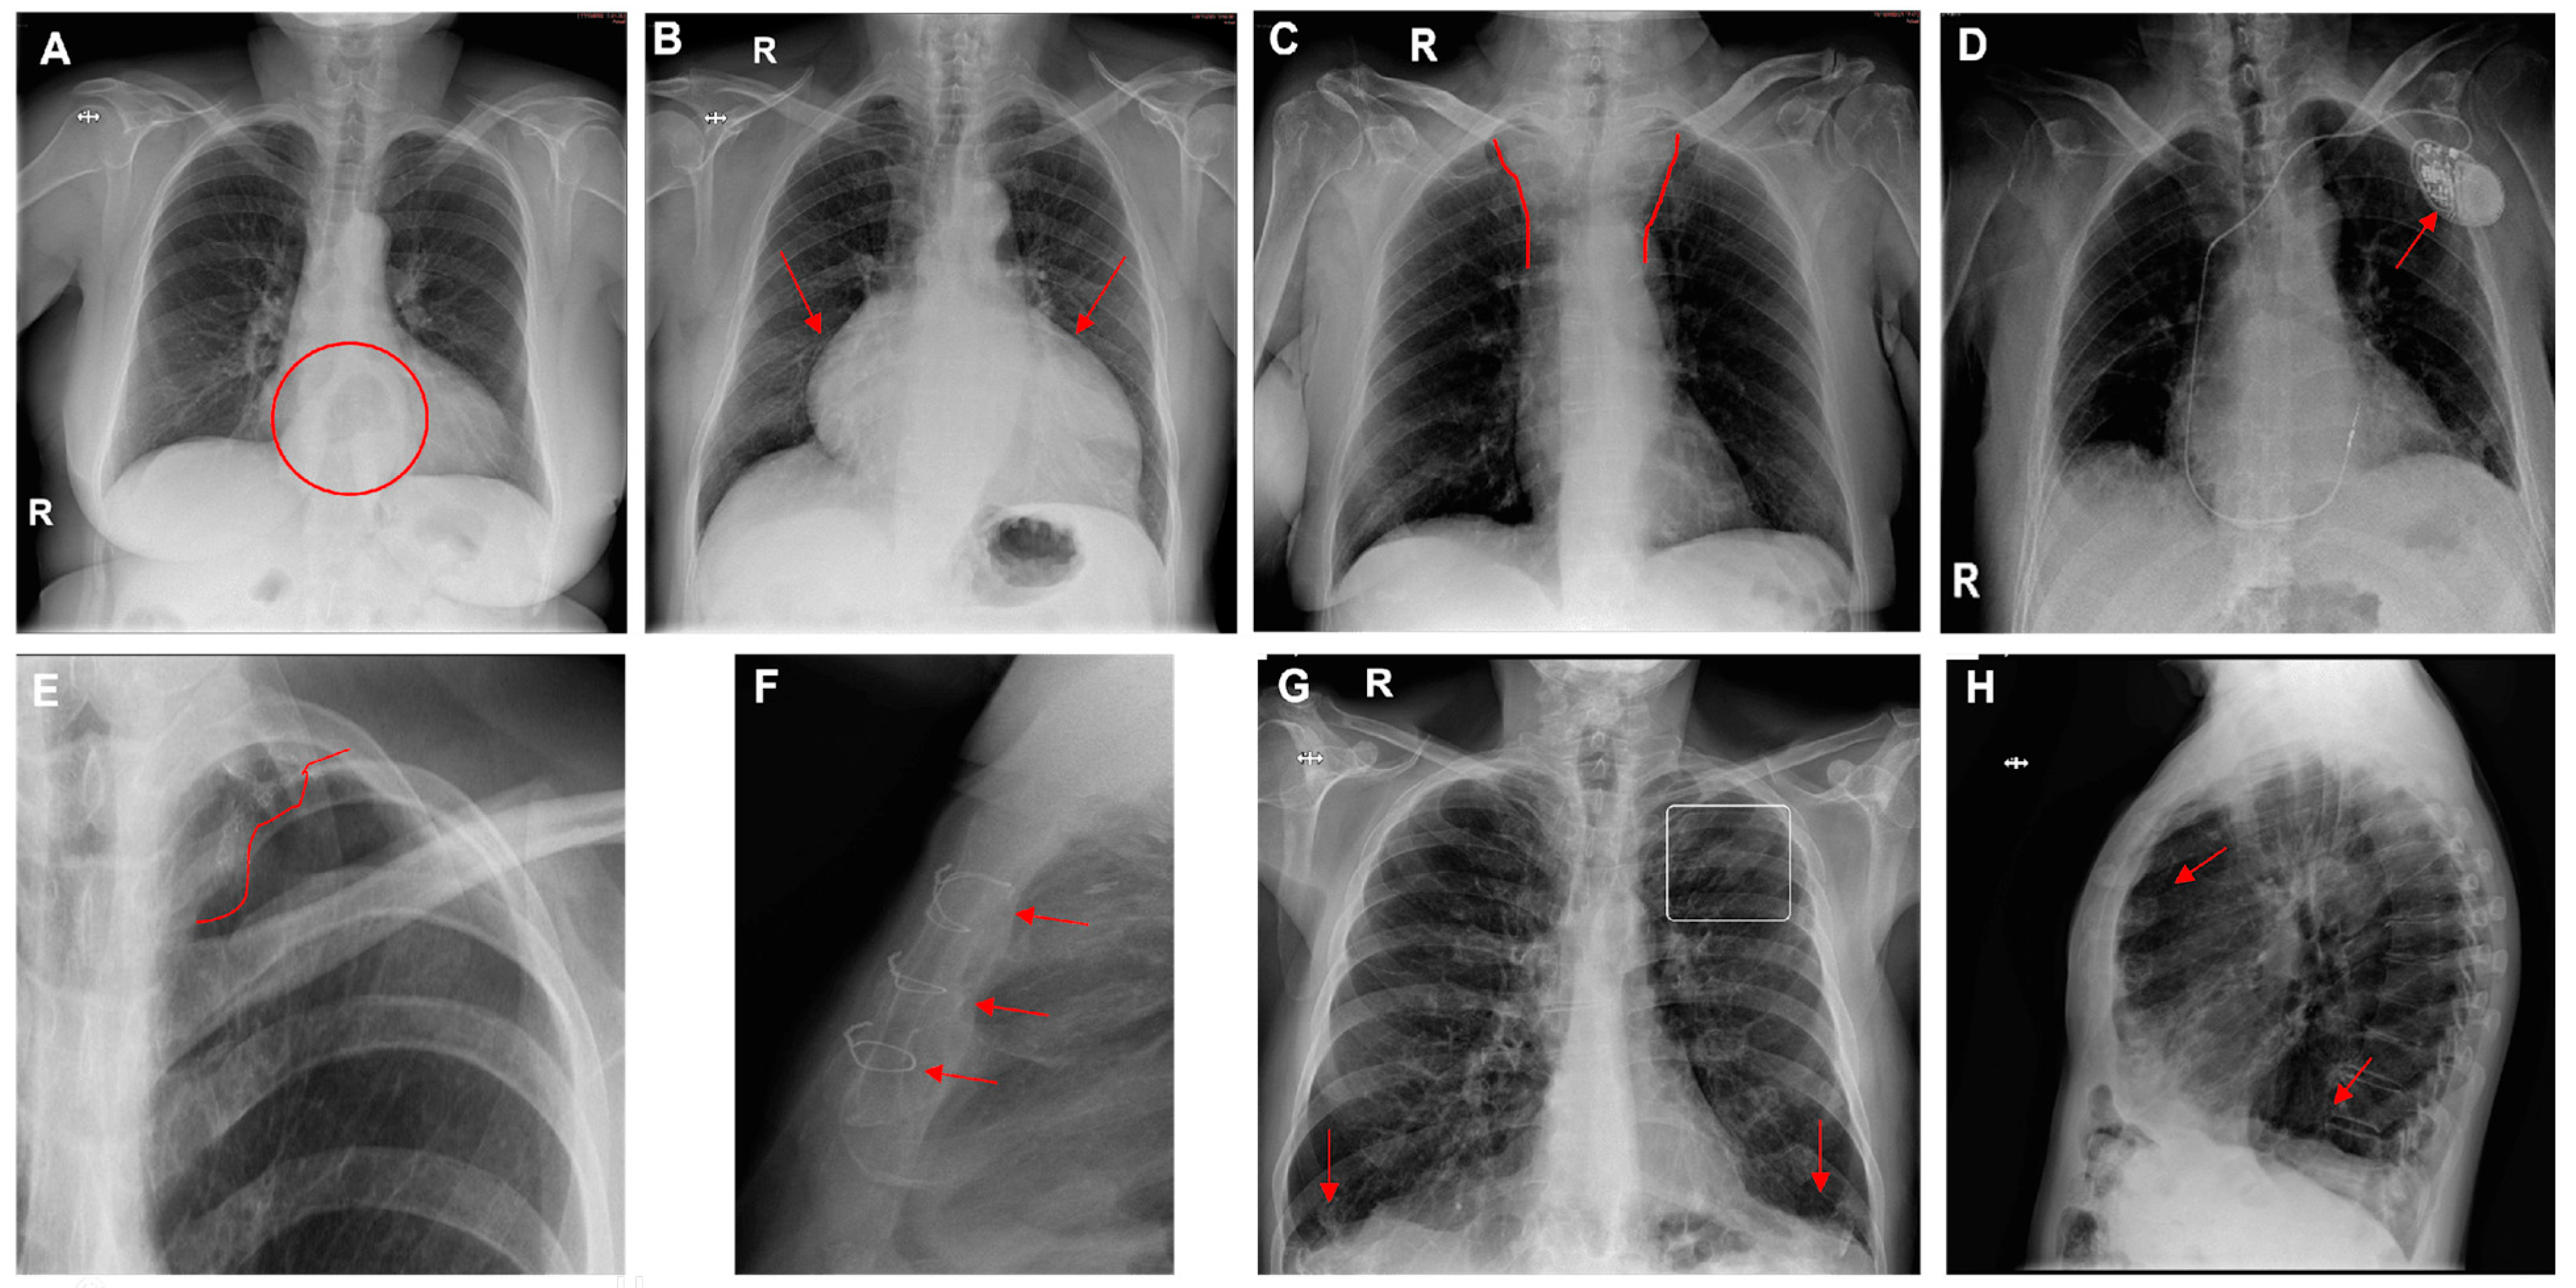

The prevalence of other variables included 16% for mediastinal abnormalities (cardiomegaly, hiatal hernia, widening of the superior mediastinum), 20% for surgical material (staples, metal valves, stents), and 20% for other pulmonary findings (pulmonary hyperinflation). Cardiomegaly was the most frequent finding (80%). Hyperinflation was found in only 7% (Figure 5 and Figure 6).

Figure 6. Chest radiographs with additional findings highlighted by red circles, arrows, or lines. (A) Hiatal hernia, (B) cardiomegaly, (C) widening of the superior mediastinum, (D) heart pacemaker, (E) pulmonary surgical material, (F) sternal surgical material, (G,H) pulmonary hyperinflation (G—flattening of the diaphragms and enlarged retrosternal space; H—enlarged retrocardiac spaces).